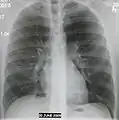

| A chest X-ray showing a very prominent wedge-shape bacterial pneumonia in the right lung | |